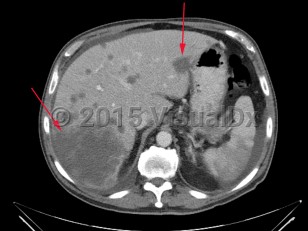

Liver cancer refers to a malignancy that arises primarily within the liver. There are several types of liver cancers. Hepatocellular carcinoma, accounting for approximately 75% of primary liver cancers, is due to malignant transformation in hepatocytes. This is most commonly seen in patients with cirrhosis of any etiology (eg, chronic viral hepatitis, alcohol-related liver disease, nonalcoholic steatohepatitis). Cholangiocarcinoma is the second most common primary liver cancer, accounting for approximately 10%-20% of cases. This is a cancer of bile duct origin.

Many malignancies can metastasize to the liver. Frequently, patients with uveal melanoma may have liver metastases. In rare circumstances, lymphomas can present with primary manifestation in the liver.